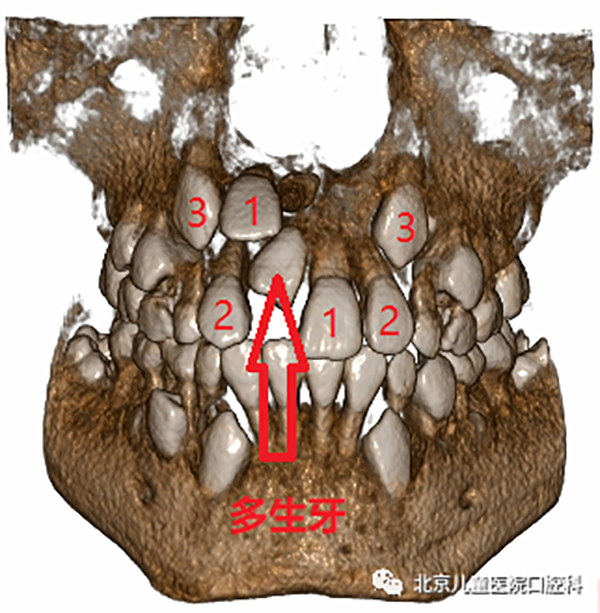

多生牙,又叫额外牙,是正常牙列以外的牙齿,发生的原因与遗传和发育障碍相关,通常在替牙期被发现,主要表现为萌出一颗畸形牙,或者新萌出的恒牙之间间隙过大,那多生牙有什么危害呢?

影响恒牙的发育和排列

多生牙可发生在牙弓任何位置,多见于上颌前牙区,通常会占用正常牙齿在牙列中的位置,破坏正常的牙弓形态,同时,由于不具备正常牙齿的外形而缺少与正常牙齿的邻接,容易造成食物嵌塞和滞留,导致牙龈组织发炎甚至引起龋齿的发生。更有甚者,占用了正常恒牙萌出的空间,挡了正常恒牙的“路”,使得正常恒牙无法顺利萌出。